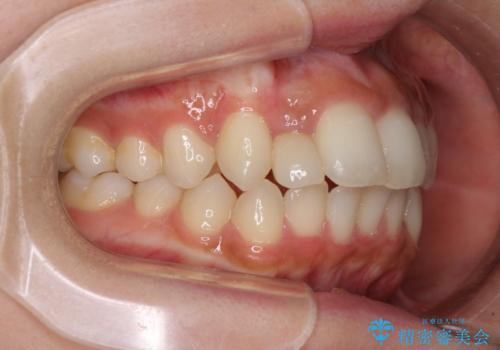

抜けてしまうと言われた前歯 インビザラインによる矯正治療

- 上下前歯のデコボコを気にして来院された患者様です。

前歯のセラミックが装着されている歯は、歯根が短くなっており、他院では抜けてしまうので矯正はできないと言われていたようです。

患者様と相談し、抜けてしまった場合にはインプラントあるいはブリッジによる補綴治療が必要となることを確認し、極力歯根に負担のかからないような仕上がりで治療を進めて行くこととしました。

デコボコを解消には、IPR(歯と歯の間を削る)をメインに歯列排列を設計し、インビザラインにて矯正治療を行うこととしました。

レントゲン写真上では、矯正治療前後で歯根長さに大きな違いはなく、抜歯を回避することができました。

上顎内側に転位している前から2番目の歯は移動が難しく、無理矢理歯根全体を動かそうと設計すると、歯肉退縮・歯髄壊死・歯根吸収といった危険性が増すため、無難なゴールにて治療を終えることとなりました。